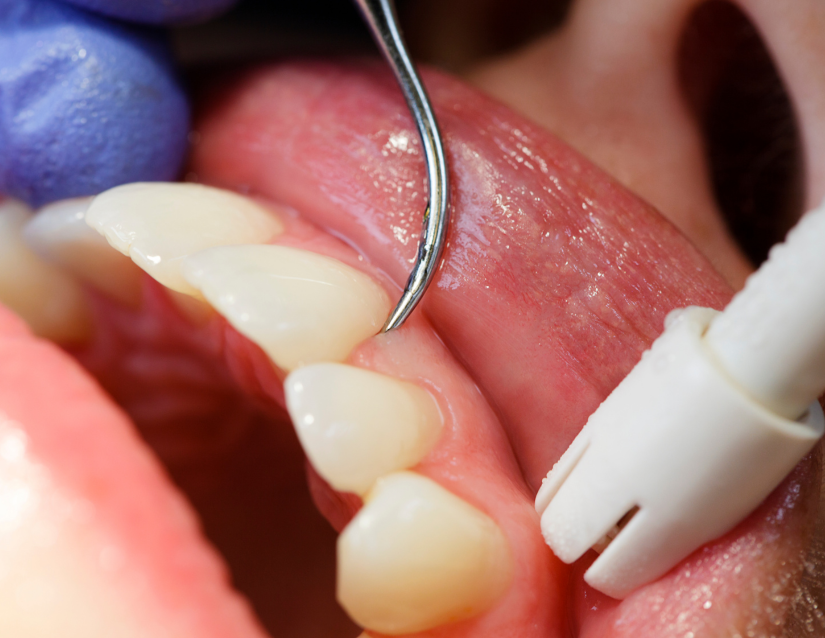

Tratamiento de Desinfección Profunda

El primer paso para detener el sangrado y la infección

Cuando las bacterias se acumulan bajo la encía, el cepillado no es suficiente. Realizamos una limpieza profunda y curetaje utilizando ultrasonido y herramientas de precisión para eliminar el sarro adherido a la raíz del diente, alisando la superficie para que la encía vuelva a sanar y adherirse firmemente.